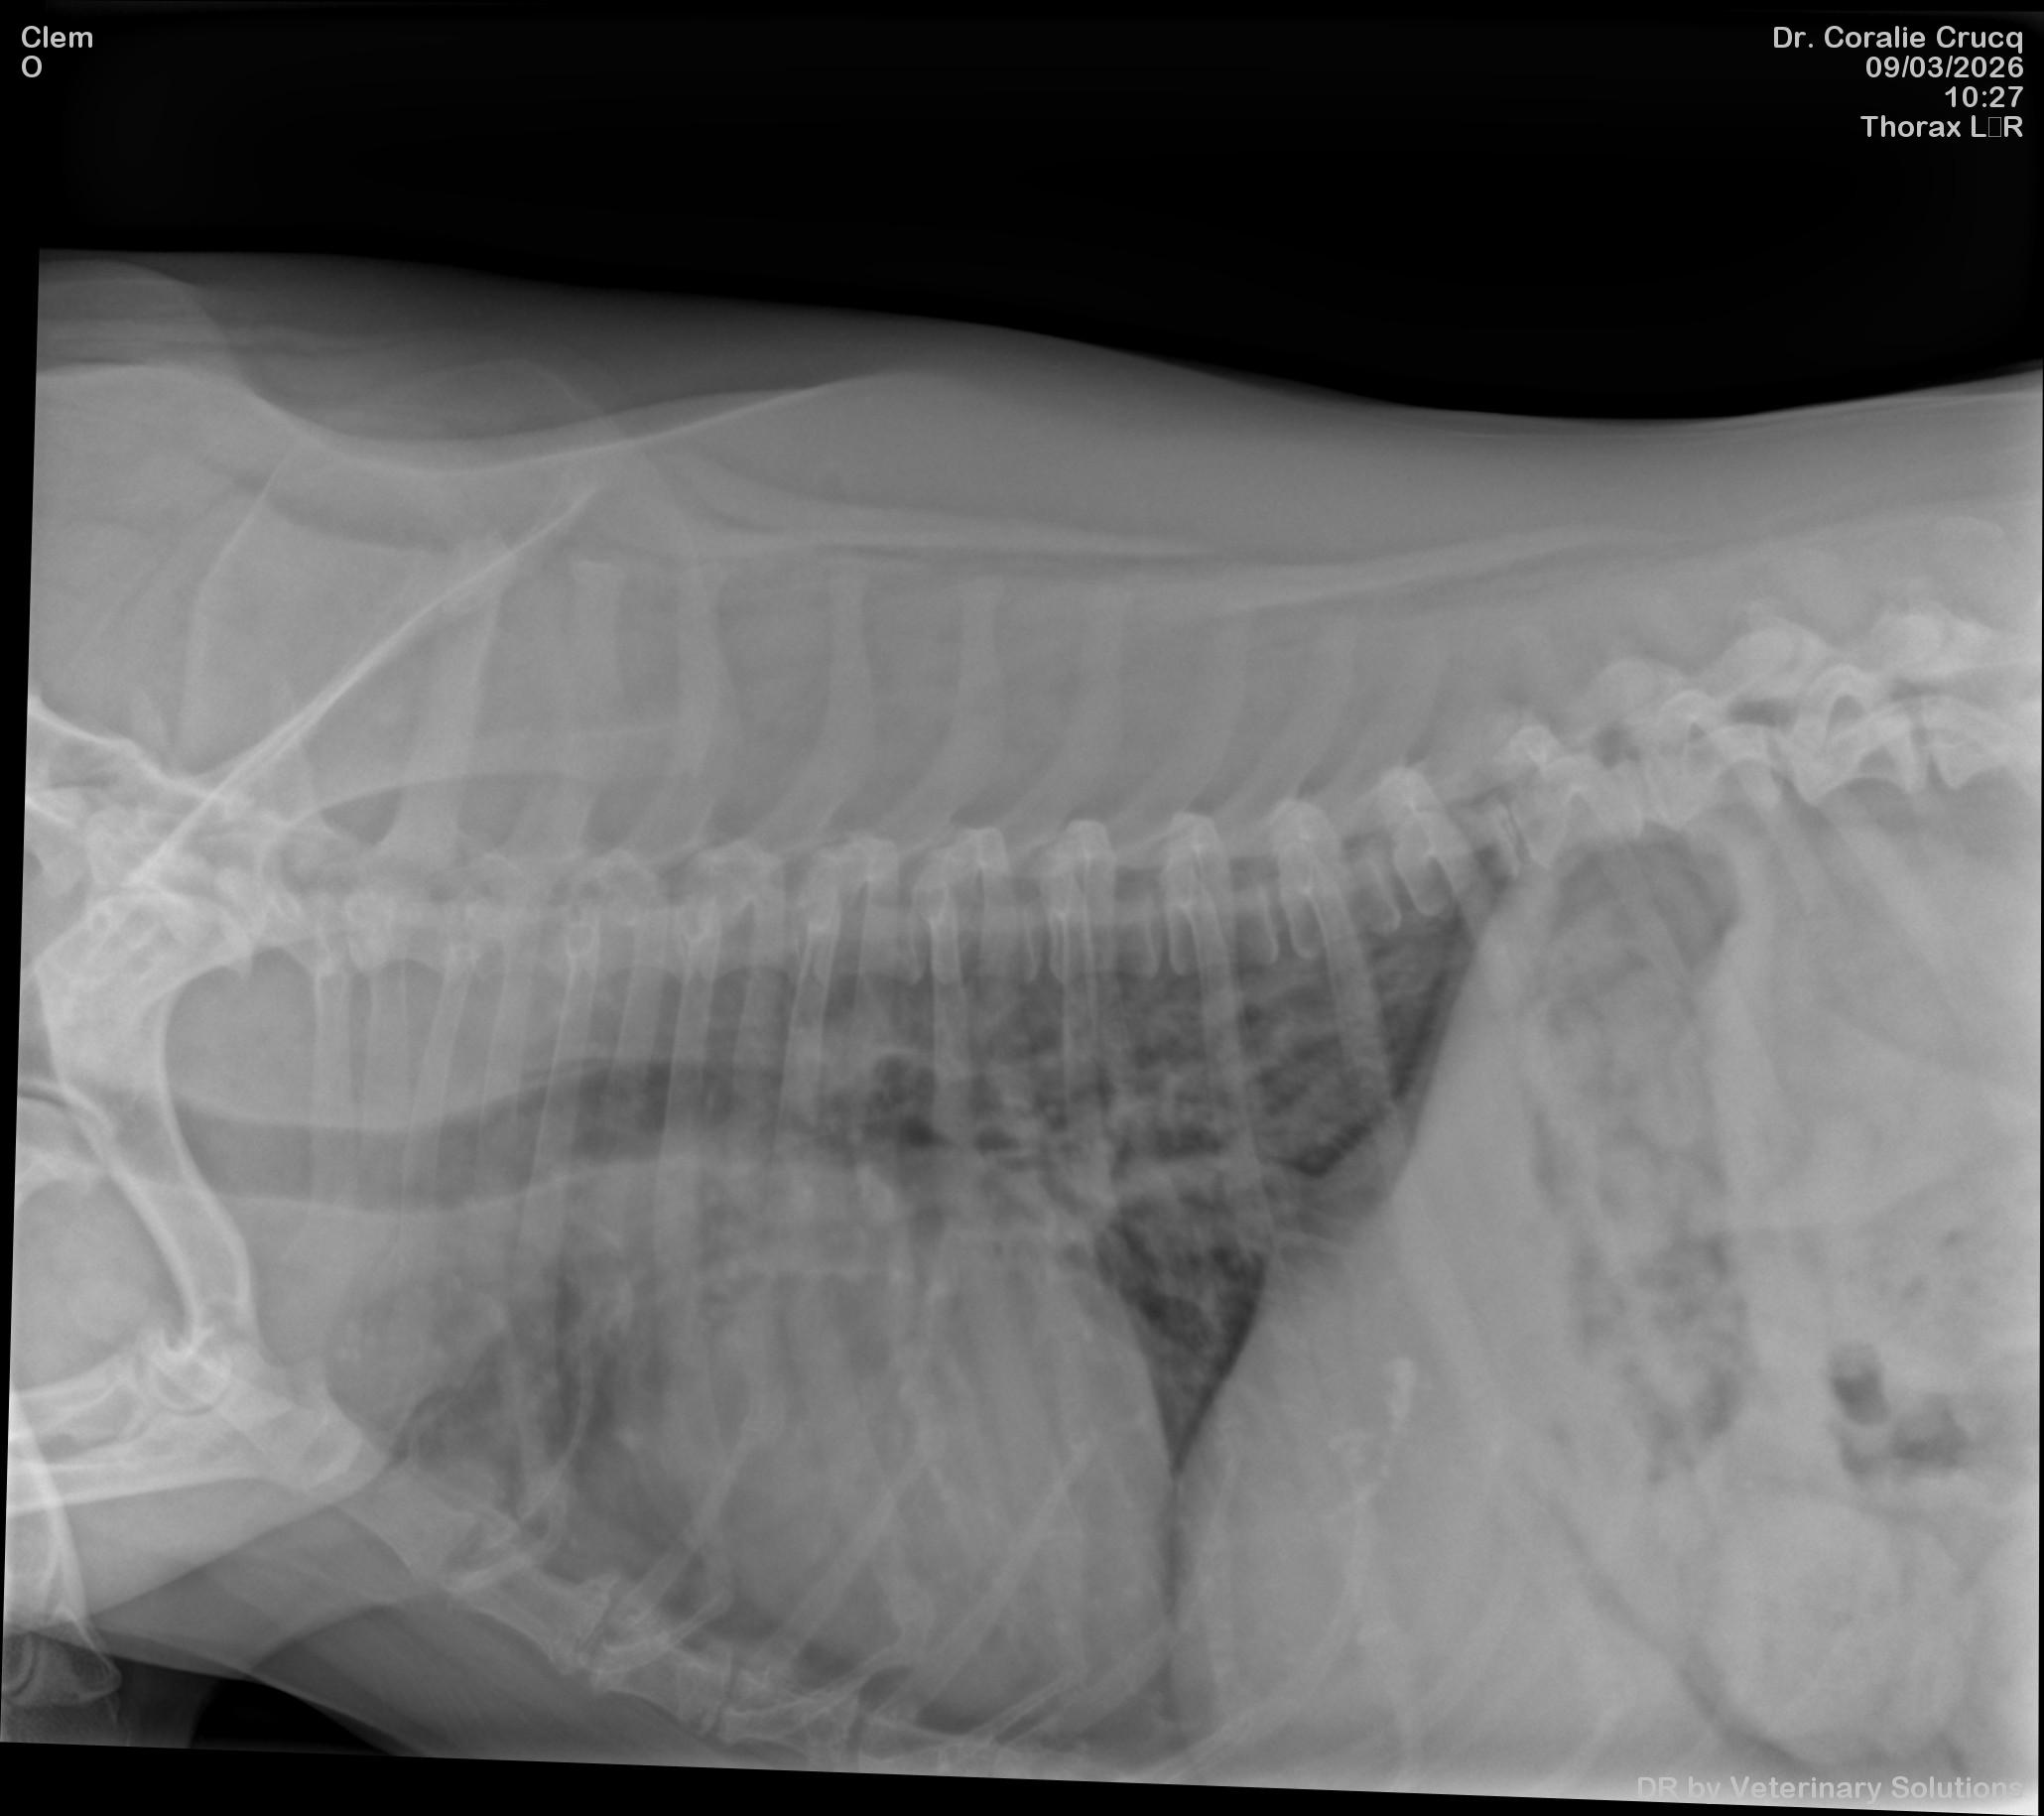

- Connaître les principaux examens à considérer chez un chien présenté en dyspnée aigue

- Connaître les limites de l’examen échographique pour l’exploration d’une dyspnée aigue chez le chien

- Connaître les limites de l’examen sanguin (mesure BNP) pour l’exploration d’une dyspnée aigue chez le chien